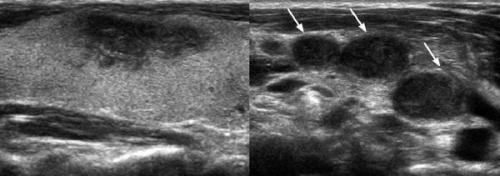

Ультразвуковое исследование в случае подострого тиреоидита показывает увеличение размеров щитовидной железы. Для женщин верхней границей нормы принято считать объём щитовидной железы 18 см3, для мужчин — 25 см3.

Ещё одним ультразвуковым признаком является наличие нечётко ограниченных зон пониженной эхогенности (показатель низкой плотности ткани железы) в виде "облака" с одной или обеих сторон, что указывает на наличие воспалительного процесса. Иногда встречается миграция этих зон.